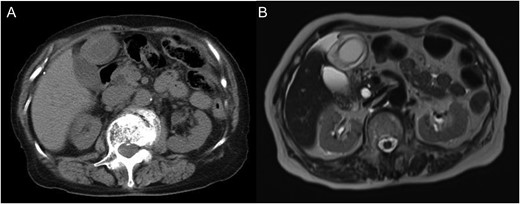

A computed tomography (CT) image revealed a gourd-shaped gallbladder with biphasic appearance divided clearly at the body. In the fundus side, the wall of the gallbladder was oedematous and thickened, while the neck side was intact (Fig. 1). The preoperative diagnosis was torsion of the gallbladder. After admission, her abdominal symptoms showed improvement, although they did not disappear completely. On the second day after onset, we planned to perform a laparoscopic cholecystectomy (LC). During laparoscopy, a tip of the omentum encircling the gallbladder was strangling the gallbladder and had adhered to the abdominal wall. By cutting the attachment site of the omentum, the strangulation was released and a whole image of the gallbladder appeared (Fig. 2). The gallbladder was found to have been strangulated by a tip of the omentum attached to the abdominal wall without torsion. The gallbladder was oedematous and congested, although it did not show apparent gangrenous change. We performed LC. The borderline between ischaemic change and non-ischaemic change in the specimen was apparent (Fig. 3).

(A) Unenhanced computed tomography image. A gourd-shaped gallbladder with biphasic appearance was revealed. In the fundus side, the wall of the gallbladder appears oedematous and thickened, while the neck side appears intact. (B) T2-weighted magnetic resonance image.